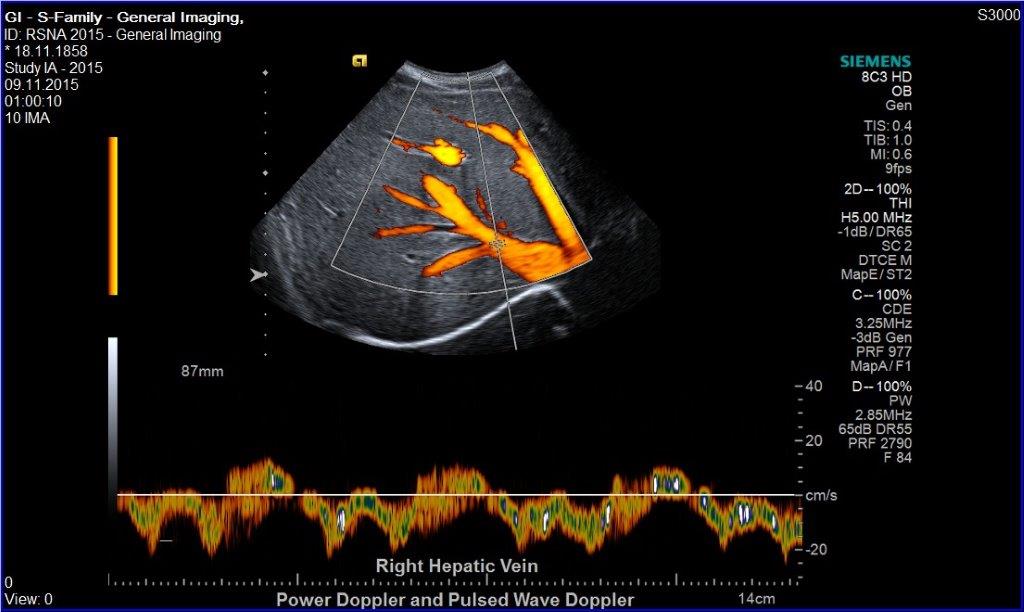

• Leber

• Gefäßultraschall